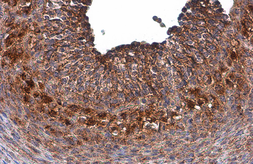

Images

Description

Applications

Reactivity